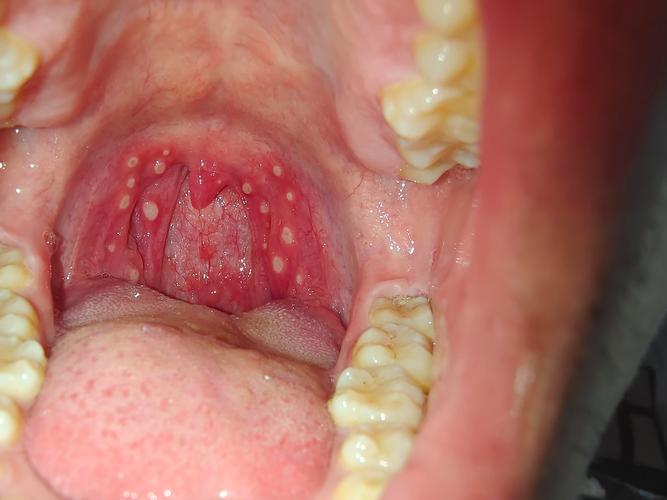

口腔溃疡长到喉咙里了 非常理解您的感受,口腔溃疡长到喉咙里,也就是我们常说的咽喉溃疡或咽部溃疡,确实非常痛苦,这比口腔里的溃疡更折磨人,因为它会直接影响到吞咽、说话甚至呼吸,疼痛感也更为剧烈。(图片来源网络,侵删) 下面我为您详细分析一下可能的原因、应对方法以及何时需要就医。 为什么会长到喉咙里? 喉咙里的溃疡和口腔溃疡...